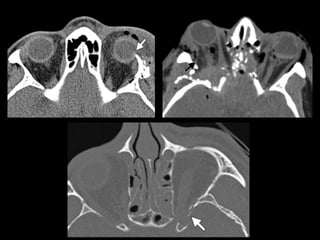

NOE

• Clasificación de Markowitz

– Tipo I: segmento central único, sin compromiso del

canto interno.

– Tipo II: segmento central conminuto, sin compromiso

del canto interno.

– Tipo III: segmento central conminuto, con

desinserción del canto interno.

NOE • Clasificación deMarkowitz – Tipo I: segmento central único, sin compromiso del canto interno. – Tipo II: segmento central conminuto, sin compromiso del canto interno. – Tipo III: segmento central conminuto, con desinserción del canto interno.

• #20 comminuted fracture of the NOE complex with telecanthus and involvement of the bilateral lacrimal fossae (arrows), findings indicative of a type III fracture of the NOE complex with medial canthal tendon avulsion. A fragment of the fractured right medial orbital wall impinges on the right optic nerve